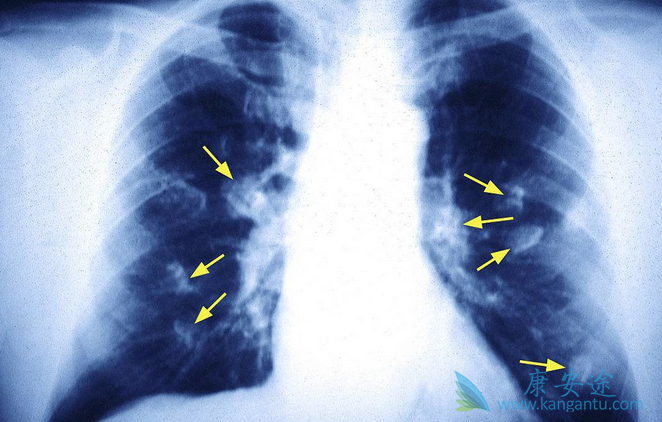

肺癌晚期治疗过程中应注意患者营养元素的摄取

肺癌晚期治疗